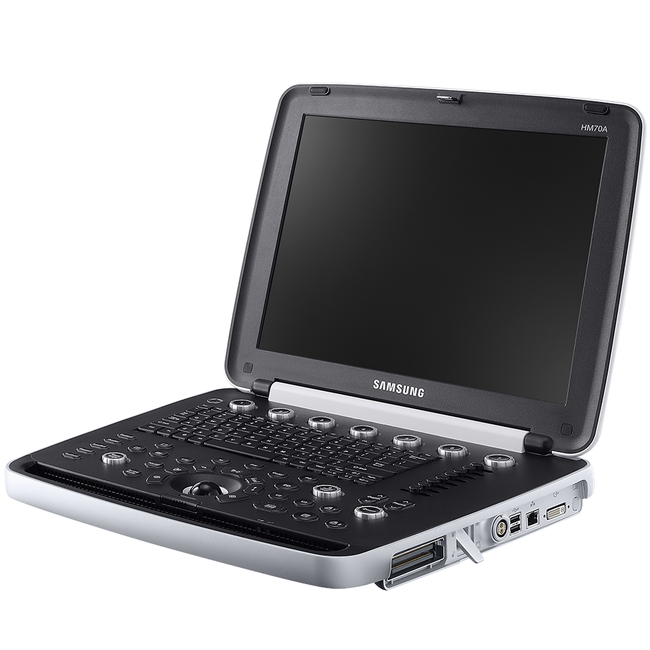

УЗИ аппараты

УЗИ аппараты

УЗИ аппараты

УЗИ аппараты

УЗИ аппараты

УЗИ аппараты

УЗИ аппараты

УЗИ аппараты

УЗИ аппараты

УЗИ аппараты

УЗИ аппараты

УЗИ аппараты

УЗИ аппараты

УЗИ аппараты